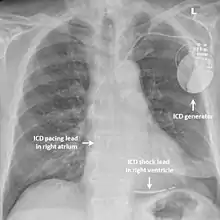

Chest x-ray of a patient with an implantable defibrillator (components labelled)

While medication and sympathectomy aim to prevent abnormal heart rhythms from occurring in the first place, an implantable defibrillator (ICD) may be used to treat arrhythmias that medication has failed to prevent and restore a normal heart rhythm.[2] These devices, usually implanted under the skin at the front of the chest below the shoulder, can continuously monitor the heart for abnormal heart rhythms. If a life-threatening arrhythmia is detected, the device can deliver a small electric shock to terminate the abnormal rhythm and restart the heart.[1]

Implantable defibrillators are often recommended for those with CPVT who have experienced blackouts, ventricular arrhythmias or cardiac arrest despite taking appropriate medication.[2] These devices are life-saving, as it has been shown that their use confers a significant survival benefit in patients with CPVT.[25] It has been suggested that the resulting surge of adrenaline caused by the pain of an electric shock from the device could theoretically bring on a cycle of recurrent arrhythmias and shocks known as an electrical storm,[4] and therefore it is strongly recommended that those with an ICD implanted for CPVT take a beta blocker to dampen the effects of adrenaline.[4]